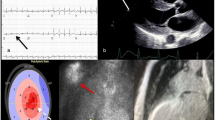

The typical ECG in cardiac amyloidosis is characterised by low QRS voltage due to amyloid infiltration, seen in approximately 50–60% in AL-CA but in only 20% in ATTR-CA [6, 8]. Therefore, an important clue is a discrepancy between the left ventricular wall thickness and QRS voltage (red flag, Tab. 2). In approximately 50–70% of patients pseudo-infarct patterns are present, eventually leading to unnecessary coronary angiography (red flag, Tab. 2; [22]). The P wave may reflect prolonged atrial conduction or atrial dilatation. Conduction disorders occur frequently, the presence of atrioventricular block in patients with left ventricular hypertrophy should raise suspicion.

Echocardiographic findings in cardiac amyloidosis are a classic example of an infiltrative cardiomyopathy. Increased echogenicity (i.e. granular or ‘speckled’ myocardium) had good sensitivity and specificity using fundamental imaging before harmonic imaging was introduced and is not reliable anymore [5, 25]. Major findings are increased left ventricular wall thickness (>12 mm, either symmetrical or asymmetrical) in combination with the right ventricular free wall, thickened valves and pericardial effusion (Fig. 2). Global longitudinal left ventricular strain analysis may reveal a pattern of prognostically important apical ‘sparing’, but the specificity for cardiac amyloidosis needs further study. Left ventricular ejection fraction (LVEF) is mostly preserved (red flag, Tab. 2; [25]). Reduced tissue Doppler velocities of the mitral annulus are common, diastolic dysfunction is frequently present including a restrictive physiology: high E/A ratio, even absence of the A wave, shortened deceleration time, high E/e’ and severely increased atrial volumes. Importantly, atrial dysfunction can also be demonstrated by an abnormal left atrial strain and may lead to the formation of thrombi even in the absence of atrial fibrillation (atrial standstill) [26].

Echocardiography in cardiac amyloidosis. a–b Granular echogenic appearance of the left ventricular wall with clear hypertrophy and some pericardial effusion. Left ventricular ejection fraction is preserved (c), septal tissue Doppler longitudinal movement is reduced (d). Longitudinal strain analysis from the 3 apical views showing characteristic apical sparing (bull’s eye) with reduced strain at the mid and basal level (e)

The advantage of CMR, besides a higher resolution, is the possibility to further characterise the myocardium using late gadolinium enhancement (LGE) imaging and T1 mapping, a quantitative technique able to detect diffuse myocardial abnormalities including amyloid burden [27]. Transmural or subendocardial LGE not fitting a coronary artery territory or including the right ventricle may be the first clue, next to suboptimal nulling due to altered gadolinium kinetics (Fig. 3). Native T1 mapping (before contrast) is typically prolonged. Postcontrast T1 mapping is decreased as the myocardial tissue reaches the null crossing at an earlier or similar inversion time as the blood pool, subsequently resulting in an increased extracellular volume (ECV) generally >40% (red flag, Tab. 2). In both ATTR-CA and AL-CA, T2 values indicative of myocardial oedema are increased and T2 is a predictor of prognosis in AL-CA [28]. CMR, similar to echocardiography, cannot differentiate between amyloidosis types.

Cardiac magnetic resonance imaging in cardiac amyloidosis. a–b Cardiac magnetic resonance imaging showing a 4‐chamber and short axis view with left ventricular hypertrophy mainly in the septal region. Corresponding short axis view showing generalised subendocardial late gadolinium enhancement not fitting a coronary territory. Note the reduced signal of the blood pool (dark blood), which is specific for cardiac amyloidosis (c). Native T1 mapping analysis showing an increased T1 value of 1214 ± 31 ms (d) and subsequent ECV map which is increased giving a value of 51 ± 2.8% (e), both acquired with a field strength of 1.5 T

Phosphate-based technetium tracers (99mTc-PYP, 99mTc-MDP, 99mTc-DPD), normally used for bone scintigraphy, accumulate in the presence of ATTR-CA although the exact mechanism is unclear. Uptake in AL-CA, Fabry disease and hypertrophic cardiomyopathy is absent or low [17]. Visual grading is based on the work by Perugini ranging from grade 0 (no uptake) to grade 3 if cardiac uptake is higher than in bone [29]. Grade 2 and 3 uptake in the absence of a monoclonal protein showed a 100% specificity and positive predictive value for ATTR-CA without the need for additional histology [30]. Importantly, in all other cases (i.e. low-grade uptake, positive light chains) cardiac and/or tissue biopsy is necessary to rule out AL-CA and more rare forms of amyloidosis (AA, AApoA1) [3]. Although positive emission tomography (PET) using 18F-Florbetapir and 11C-PiB to image β‑amyloid looks promising, it is not routinely used yet [31, 32].